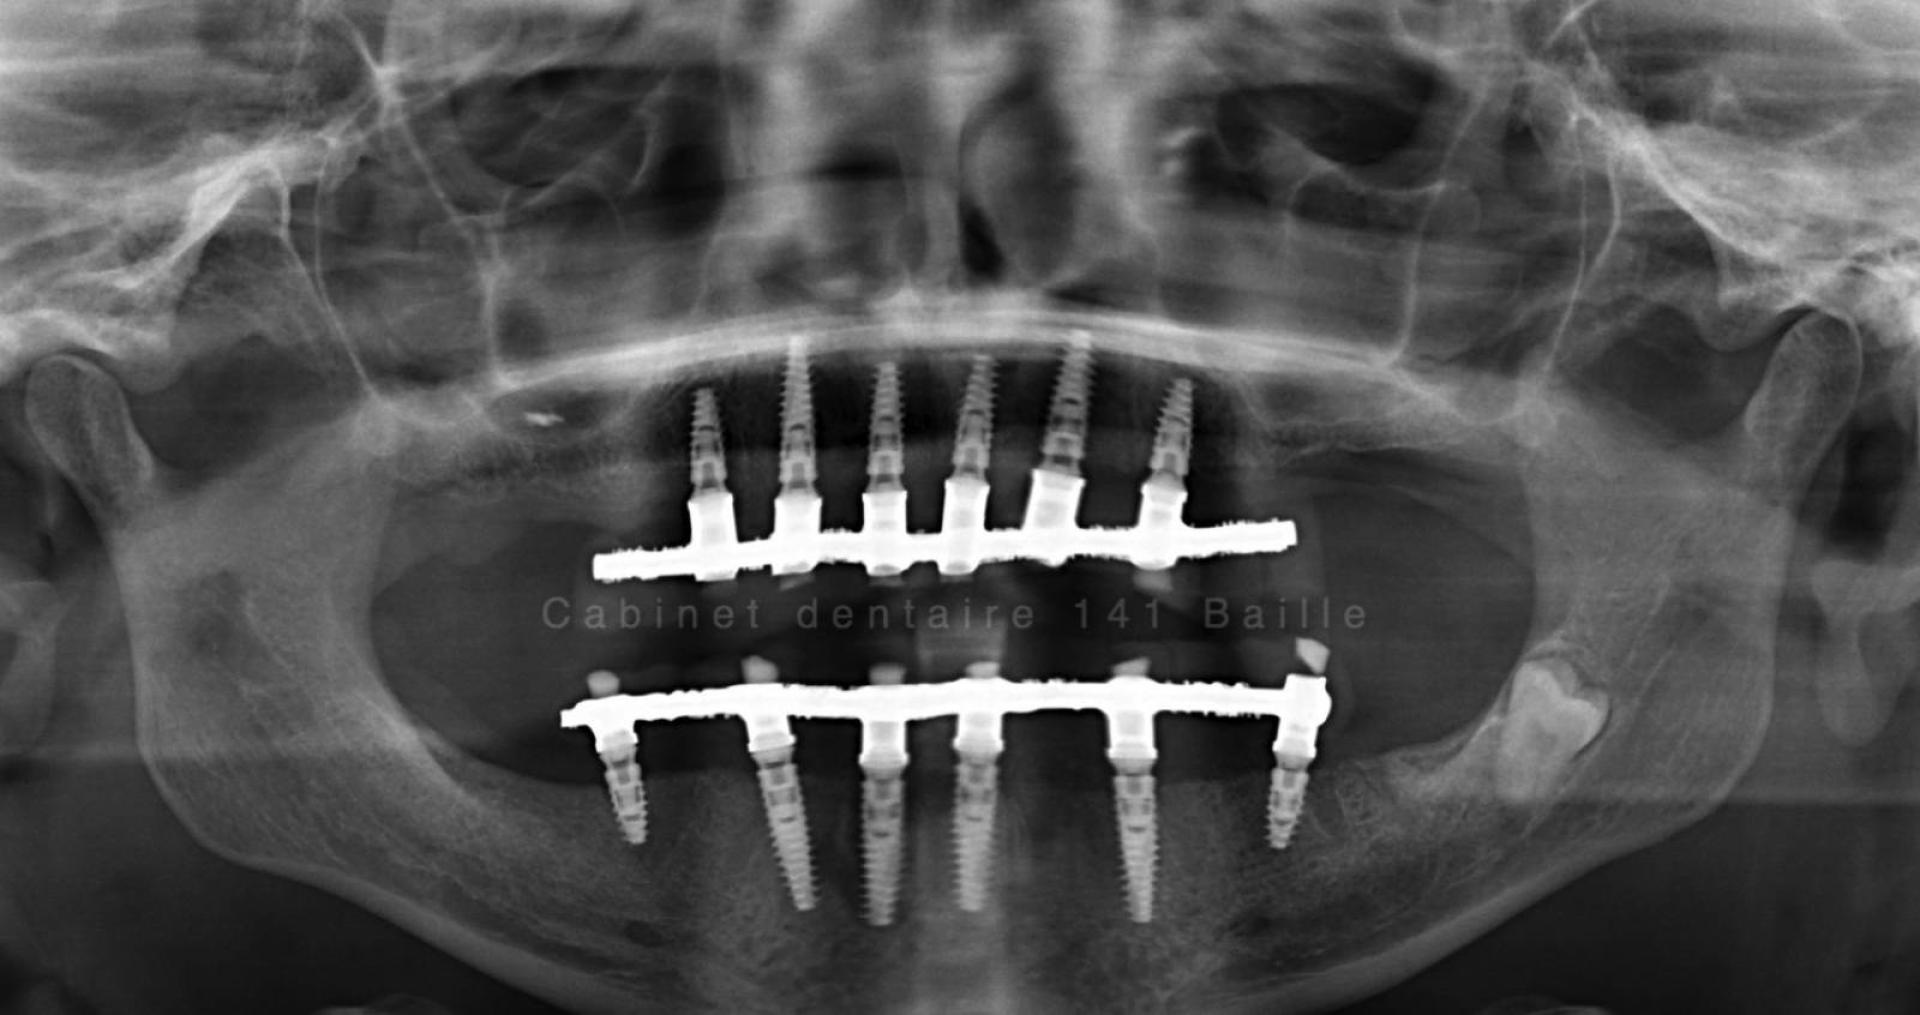

L'implant dentaire est une sorte de cheville que le chirurgien dentiste implantologue place dans l'os alvéolaire.

La tenue de l'implant est conditionnée par des facteurs de biomécanique ,qui dépendent essentiellement de la qualité de l'os et de sa quantité sur le site receveur de l'implant.En cas de manque de volume osseux ,il sera impossible sans réaliser de greffe osseuse dentaire préalablement à la pose de l'implant d'envisager ce type de technique.

On parle alors de Régénération Osseuse Guidée (ROG).Ces techniques de chirurgie avancée pré-implantaire ont énormément évolué et permettent aujourd'hui d'étendre les possibilité du traitement par implant dentaire aux patients ayant eu une forte perte d'os.

Le principe est de créer  un volume d'os plus important par des techniques de coffrage et d'isolation par des membranes spécifiques qui permettent à l'os alvéolaire de se différencier sans être envahi par les cellules de la gencive.

On est dans des techniques de chirurgie osseuse avancées qui nécessitent un environnement stérile et des compétences particulière de la part du chirurgien implantologue.